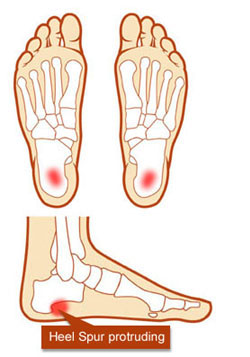

Sabahleyin yataktan kalktığınızda, ilk birkaç adımınız, ayak topuğunuz içinde, şiddetli ağrıya neden oluyorsa, sizde plantar fassitis mevcut olabilir. Bu durum* tabanınızın veya ayağınızın fleksör yüzünün (plantar) fazla kullanılmasından kaynaklanan bir incinmedir. Bir plantar fassitisin teşhisi, sizin topuk kemiğinizi ayak parmaklarınızın taban kısmına (alt kısmına) bağlayan dokunun(fasya) fibröz bantlarının çok kötü bir inflamasyonu anlamına gelir.

Eğer kadınsanız, kilonuz normalin üzerindeyse veya oldukça fazla yürümenizi veya ayakta sert zeminde kalmanızı gerektiren bir işiniz varsa, bu duruma gelmeniz daha fazla muhtemeldir. Egzersiz için koştuğunuzda ve yürüdüğünüzde de özellikle ayak bileğinizi bükmenizi oldukça kısıtlayan, sert baldır kaslarınız varsa risk altındasınızdır. Düz ve yayvan ayakları olan veya çok yüksek ayak kavsi olan insanlar, daha da fazla plantar fassitise eğilimlidirler. Bu durum, kademe kademe, topuk kemiğinde orta derecede bir ağrıyla başlar ve sıklıkla, ve ayağın bir taşla berelenmesiyle ilgilendirilir.

Bu ağrıyı egzersiz sırasında değil de, daha çok egzersizden sonra daha fazla hissetmeniz olasıdır. Ağrı klasik olarak, tekrar öğle vakti yemek molası sırasında artarak ortaya çıkar. Eğer plantar fassitinizi tedavi ettirmezseniz, kronik bir duruma dönüşebilir , aktivitelerinizi aynı seviyede tutamayabilirsiniz ve plantar fassitis sizin yürüyüş şeklinizi değiştireceği için; ayak, diz, kalça ve sırt problemlerinizden ötürü semptomlarınızı geliştirebilirsiniz.

Bu bölgede ağrılar topuktan başparmağa uzanan plantar fasia olarak adlandırılan adalede oluşur. Plantar fasitis (subkalkaneal ağrı): Çok fazla koşma ve zıplama, ayak parmaklarından topuk kemiğine uzanan adale bantlarının (fascia) inflamasyonuna neden olur. Ağrı topuğunuzun altında ve merkezinde toplanır, başlangıçta orta derecededir, fakat gece boyunca dinlenmenizden sonra ilk adımı attığınızda, aniden şiddetlenir. Topuk Dikeni)

Plantar fasiitis uzun süre devam ederse fascia doku bantlarının topuğa bağlandığı yerde, bir topuk dikeni (kalsiyum tortusu) şekillenir. Bu kolaylıkla çekilen bir röntgende görülebilir. Tedavi çoğunlukla, plantar fasiitisle aynıdır.

Sol taraftaki resme bakarak sizlere anlatmak istiyorum.Kırmızı kalemle yuvarlak içine alınan kalsiyum tortusunu dorn terapi yöntemiyle dağıtıyoruz.Dağıttıktan sonra o bölgede acıya neden olan siniri (el terapi) yöntemiyle mavi yuvarlağın içersine birkaç maniplasyon hareketiyle yerine getiriyoruz..Pelvis kemiklerini dengeye getirdikten sonra bir kaç dakikalık masaj tekniği ile sorunlu bölge ortadan kalkıyor.Ayağa kalktığınız da daha ilk seansta yüzünüz gülmeye başlıyor ve ayağınızın topuğunu korkusuzca yere basıyorsunuz.Terapi olmak için hala bekliyormusunuz?